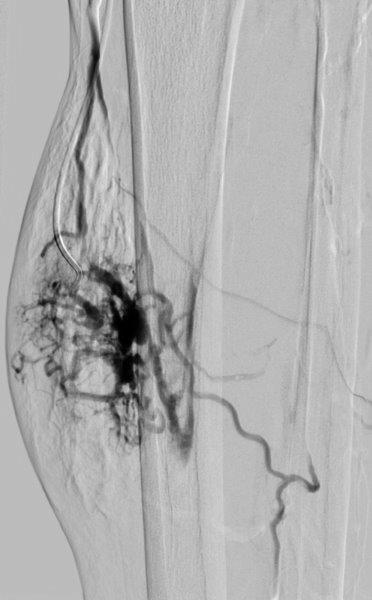

Man unterscheidet Gefäßmalformationen mit einem schnellen Blutfluss („fast-flow“) und einem sehr langsamen Fluss („slow-flow“). Zu Erstgenannten gehören Fehlbildungen mit Beteiligung der Schlagadern (Arterien), zu Letztgenannten werden venöse, kapilläre und lymphatische Gefäßfehlbildungen gezählt. Die Diagnostik Apparative Diagnostik sowie Therapieplanung erfolgt mit Hilfe von Sonographie, MRT und Angiographie.

Im Laufe der Zeit haben sich verschiedene Behandlungstechniken etabliert. Während früher die chirurgische Therapie oder Bestrahlung im Vordergrund standen, hat sich heutzutage insbesondere die mikroinvasive radiologische Therapie etabliert. Hier werden die transarterielle oder transvenöse Embolisation und die bildgesteuerte Direktinjektion von speziellen Flüssigkeiten zu Verklebung (Sklerosierung) der Gefäßmalformation eingesetzt.

Je nach Typ und Lage der Gefäßmalformation erfolgt der Eingriff über die Leistenarterie (transarteriell), die Leistenvene (transvenös) oder durch eine bildgesteuerte Direktpunktion durch einen interventionellen Radiologen. Danach wird ein dünner Katheter in die Gefäßfehlbildung eingebracht. Hierüber werden die zuführenden Gefäße entweder mit kleinen Metallspiralen oder einem bioverträglichen Klebstoff verschlossen. Da diese Veränderungen häufig mehrere Zu- und Abflüsse haben ist in vielen Fällen eine wiederholte Behandlung notwendig. In ausgewählten Fällen ist eine Kombination aus einer Verödung und einer nachfolgenden operativen Entfernung die beste Behandlungsoption. Wir führen diese Therapie daher in enger Kooperation mit den chirurgischen Kliniken unseres Hauses durch.